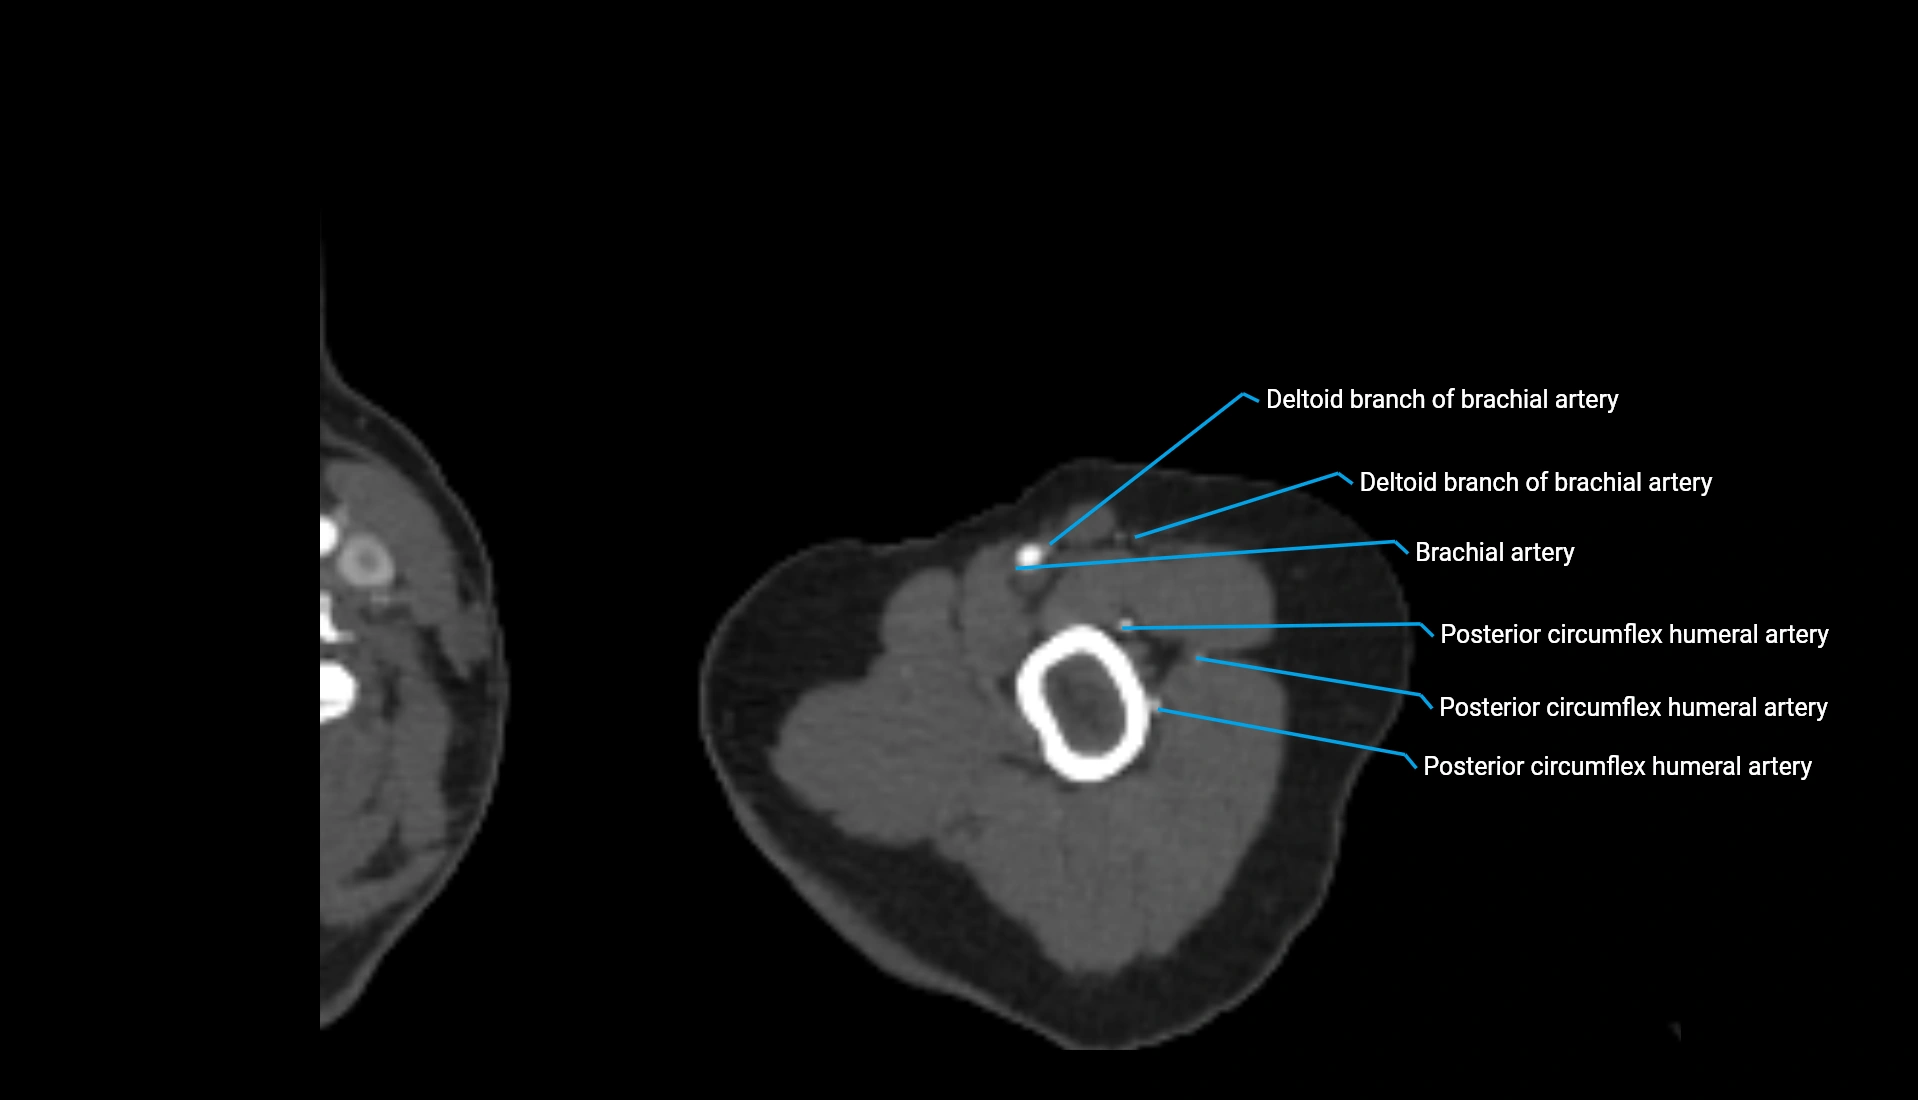

CT Appearance

Non-Contrast CT:

• Cortex: High-density, sharply defined

• Subchondral bone: Dense cancellous matrix

• Articular surface: Smooth concave contour articulating with the capitellum

• Excellent for evaluating bone integrity, alignment, and subtle fractures